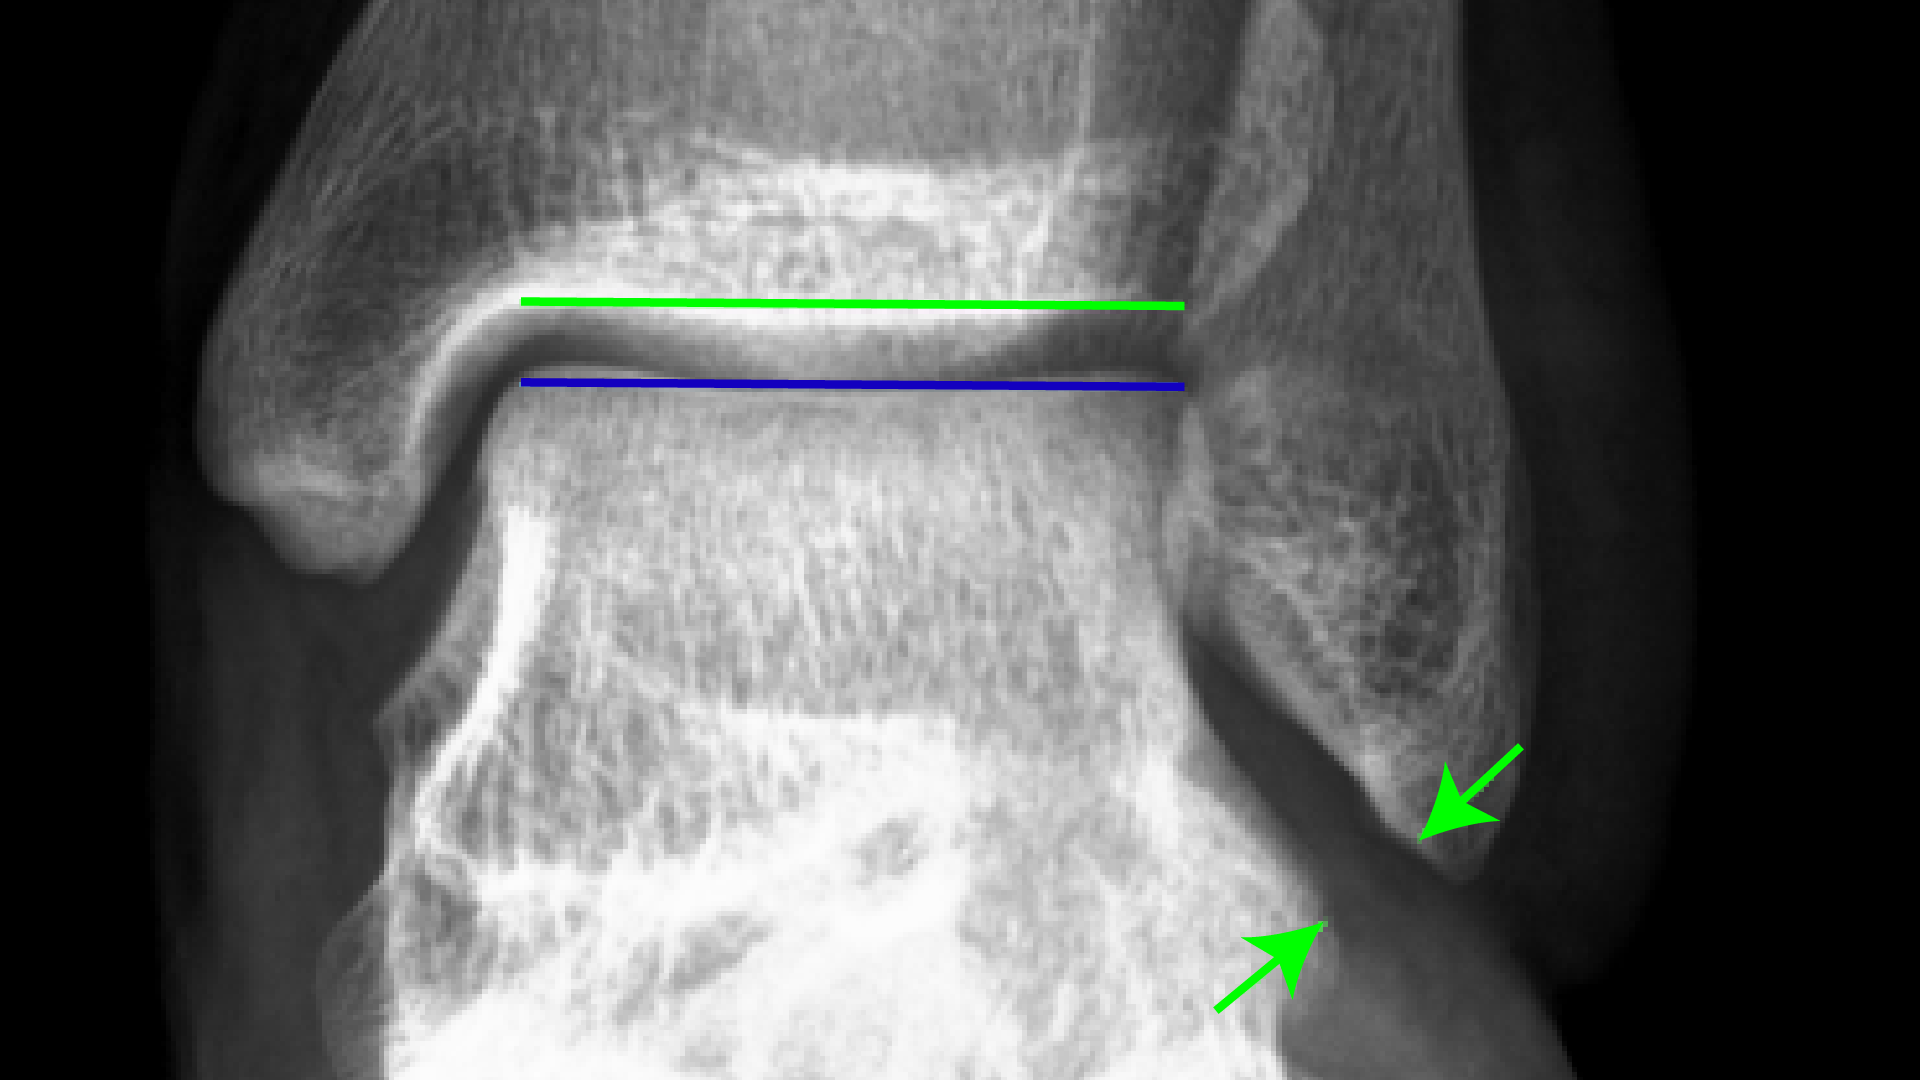

From www.wjgnet.com

Acute syndesmotic injuries in ankle fractures From diagnosis to X Ray Criteria For Ankle Injury Bone tenderness at the base of the 5th metatarsal. The ankle series is comprised of an anteroposterior (ap), mortise and lateral radiograph. Acute injuries to the ankle are frequently encountered in the setting of the emergency room, sport, and general practice. The series is often used in emergency departments to evaluate the distal tibia,. X Ray Criteria For Ankle Injury.